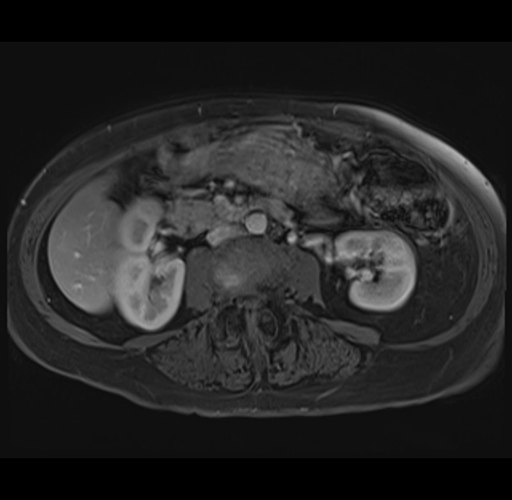

MRI T1

Imaging analysis